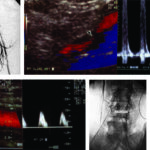

De no contar con información sobre el tipo de cirugía realizada, el médico radiólogo llevará a cabo una anamnesis al paciente sobre el tema y la sintomatología actual; asimismo lo examinará en búsqueda de cicatrices que le permitan reconocer la técnica empleada. Luego procederá a evaluar el tipo de injerto y la topografía del bypass, realizará la medición de las velocidades de flujo en las anastomosis y en el injerto, y procederá a medir el índice tobillo-braquial. Identificará el tipo de bypass femoral. Durante el examen se evaluará la velocidad de pico sistólico en el sector de las anastomosis y en el injerto. En el período postquirúrgico el flujo típico es de hiperemia, con diástoles prominentes. Al cabo de dos meses se establece un patrón trifásico típico. La velocidad en el bypass debe ser superior a 40 cm/seg (Fig. 21).

Angioplastia con stent ilíaco

Se utiliza en las estenosis de las arterias ilíacas, su colocación a nivel femoral o poplíteo no tiene buenos resultados a largo plazo, se utilizan en pacientes con alto riesgo quirúrgico10 (Fig. 22).